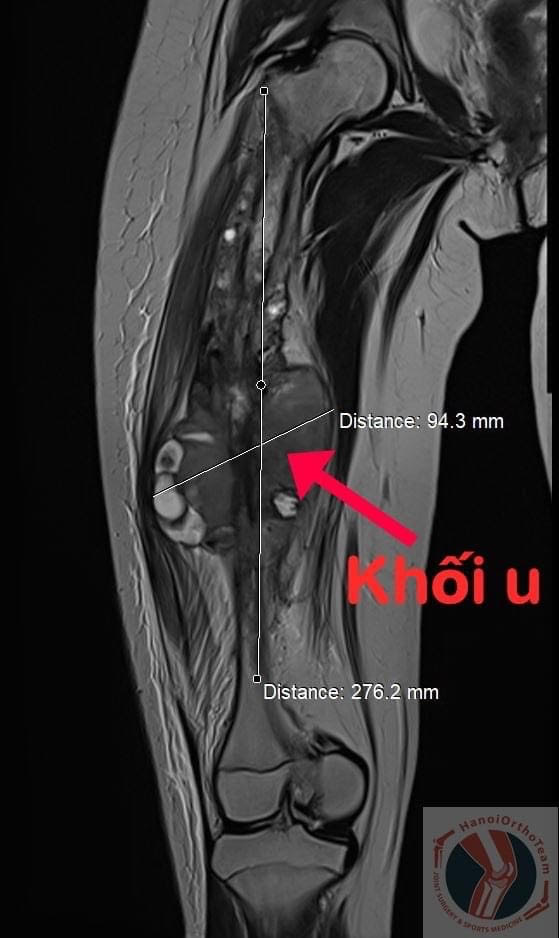

Chiều ngày 22/2/2021, các bác sĩ, chuyên gia tại Trung tâm Phẫu thuật Khớp và Y học thể thao, Bệnh viện đa khoa Tâm Anh, Hà Nội đã thực hiện thành công ca phẫu thuật thay thế toàn bộ xương đùi cho bệnh nhi chỉ mới 11 tuổi để điều trị ung thư xương. Được biết đây là trường hợp thay xương nhân tạo trẻ nhất tại Việt Nam từ trước đến nay.

Bệnh nhân Q.A, 11 tuổi, nhà ở Thành phố Hồ Chí Minh, đau đùi phải âm ỉ tăng dần suốt 1 năm nay. Gia đình cho cháu đi khám tại Bệnh viện Nhi Đồng được chẩn đoán ung thư xương đùi và được chuyển sang Bệnh viện Ung bướu Thành phố Hồ Chí Minh để tiếp tục điều trị.

Thật không may mắn, sau đợt điều trị hóa chất đầu tiên, khối u không những không đáp ứng thuốc mà còn phát triển lớn hơn dẫn đến xâm lấn, làm gãy đôi thân xương đùi khiến cháu phải bó bột toàn bộ chân phải. Đồng thời, cháu vẫn phải tiếp tục điều trị các đợt hóa chất theo phác đồ để chuẩn bị cho cuộc phẫu thuật lấy bỏ khối u sắp tới.

Trong thời gian này, Q.A phải ngồi xe lăn bất động tại chỗ, luôn phải có người thân giúp cháu chăm sóc, vệ sinh cá nhân; đồng thời phải chịu đựng một nỗi đau dai dẳng hành hạ suốt đêm ngày. Lúc này, các bác sĩ đánh giá lại sau 3 đợt điều trị hóa chất thấy bệnh của cháu không thuyên giảm mà còn có dấu hiệu u tiếp tục to ra.

Tới khám tại Trung tâm Phẫu thuật Khớp và Y học thể thao, Bệnh viện đa khoa Tâm Anh, GS.TS Trần Trung Dũng, phụ trách chuyên môn của trung tâm đã nhận định rằng: "Ung thư xương ở lứa tuổi trẻ em là một bệnh lý có tính chất ác tính rất cao, không chỉ khiến bệnh nhân có nguy cơ tàn phế mà thậm chí còn nguy hiểm đến tính mạng".

"Đối với trường hợp cháu Q.A, khối u đã phát triển quá mức dọc theo thân xương đùi và xâm lấn "ăn" gãy đôi thân xương. Do đó, giải pháp duy nhất là phải tháo bỏ toàn bộ xương đùi kèm theo khối u. Nhưng nếu không có giải pháp thay thế vị trí khuyết của xương thì nguy cơ phải cắt bỏ chân của cháu để cứu tính mạng là rất cao! Tuy nhiên, do cháu còn quá nhỏ và gia đình cũng khát khao đặt nhiều niềm tin vào việc bảo tồn chân cho con nên chúng tôi cần tìm ra một giải pháp phù hợp nhất cho cháu", GS.TS Trần Trung Dũng nói.

Trải qua đợt điều trị hóa chất tiền phẫu và ca đại phẫu kéo dài gần 3 tiếng đồng hồ, cuối cùng các bác sĩ đã lấy bỏ xương đùi bị bệnh cùng khối u khổng lồ có kích thước 28x10cm, nặng gần 3kg của bệnh nhân ra khỏi cơ thể. Đồng thời, thay thế thành công xương đùi nhân tạo kèm khớp háng và khớp gối nhân tạo.